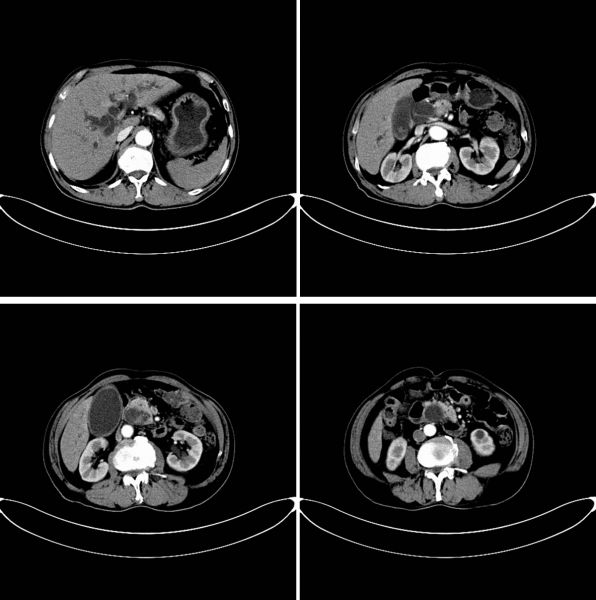

患者李大爷平时身体一向不错,前段时间食欲不佳、经常腹胀且小便发黄,本以为是消化不良,但服用消化药后症状并没有缓解。于是,李大爷在家属的陪同下来到我院肝胆一科外科就诊,经检查后发现:胆红素升高,腹部CT结果显示胰腺头部囊性占位合并胆道梗阻,家属当即办理了住院手续。

入院后,肝胆一科副主任王文儿领衔的治疗团队继续为李大爷完善检查,腹部增强磁共振和增强CT共同提示为胰头囊性肿瘤,须手术治疗。

术前CT